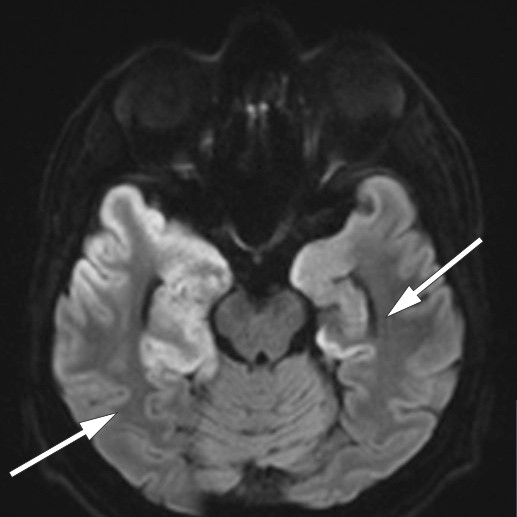

The EEG showed pathological slowing of background activity and bursts of delta activity in temporal regions, consistent with encephalitis (6, 7). A head MRI performed six days after admission showed widespread changes over the temporal lobes, including the hippocampus, typical of herpes encephalitis (8) (Figure 2, Figure 3a).

A week after initiation of immunoglobulin therapy, high NMDA receptor antibody titres were confirmed in the patient's CSF. Another brain MRI four weeks after the first showed increasing hyperintensities in both temporal lobes. This finding is not specific to either herpes encephalitis or autoimmune encephalitis (11).